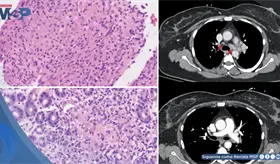

El estudio histológico confirmó un adenocarcinoma mucinoso de células en anillo de sello de vejiga con invasión muscular y diseminación metastásica pulmonar y ósea.